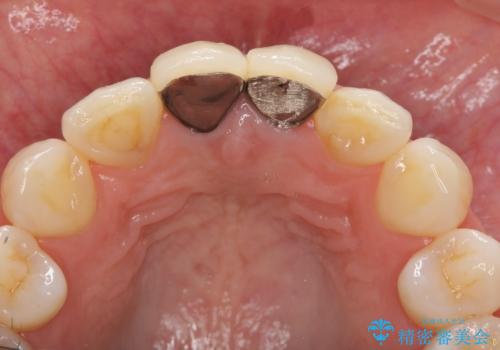

- 「幼少期に転んで治療した前歯がうずく、疲れると膿が出る。」と治療を希望され来院されました。

X線写真検査に加え圧痛、打診痛が認められたため、慢性根尖性歯周炎と診断し、根管治療から行うセラミック治療を計画します。

- 26.2万円(仮歯・ファイバーコア・ジルコニアクラウン×2)費用は治療当時の料金となります

根管治療について

歯ぐきを押すと痛い、うずく、響く、などの症状は感染根管による根尖性歯周炎や歯の破折の所見であることが多々見られます。